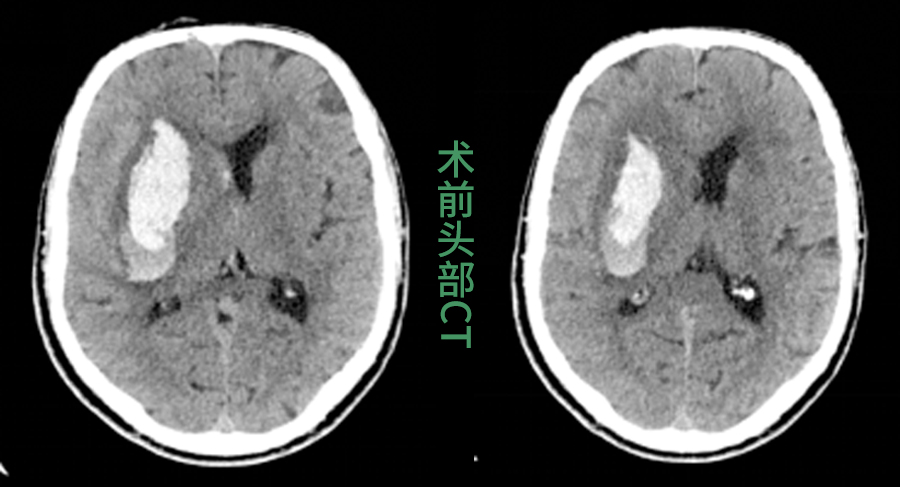

脑出血起病急、致死致残率高,及时清除血肿是拯救生命的关键。传统的穿刺引流术虽属微创,但医生只能在二维CT影像的指引下,凭借临床经验徒手进行穿刺。这个过程存在一定的不确定性,如同在没有导航的复杂路况中行车,难以确保每次都能“一击即中”。

1.三维重建,虚拟规划:术前,医生将患者的颅脑CT数据输入计算机,生成一个颅内三维数字模型,血肿的形态、深度及其与关键组织的比邻关系清晰呈现。